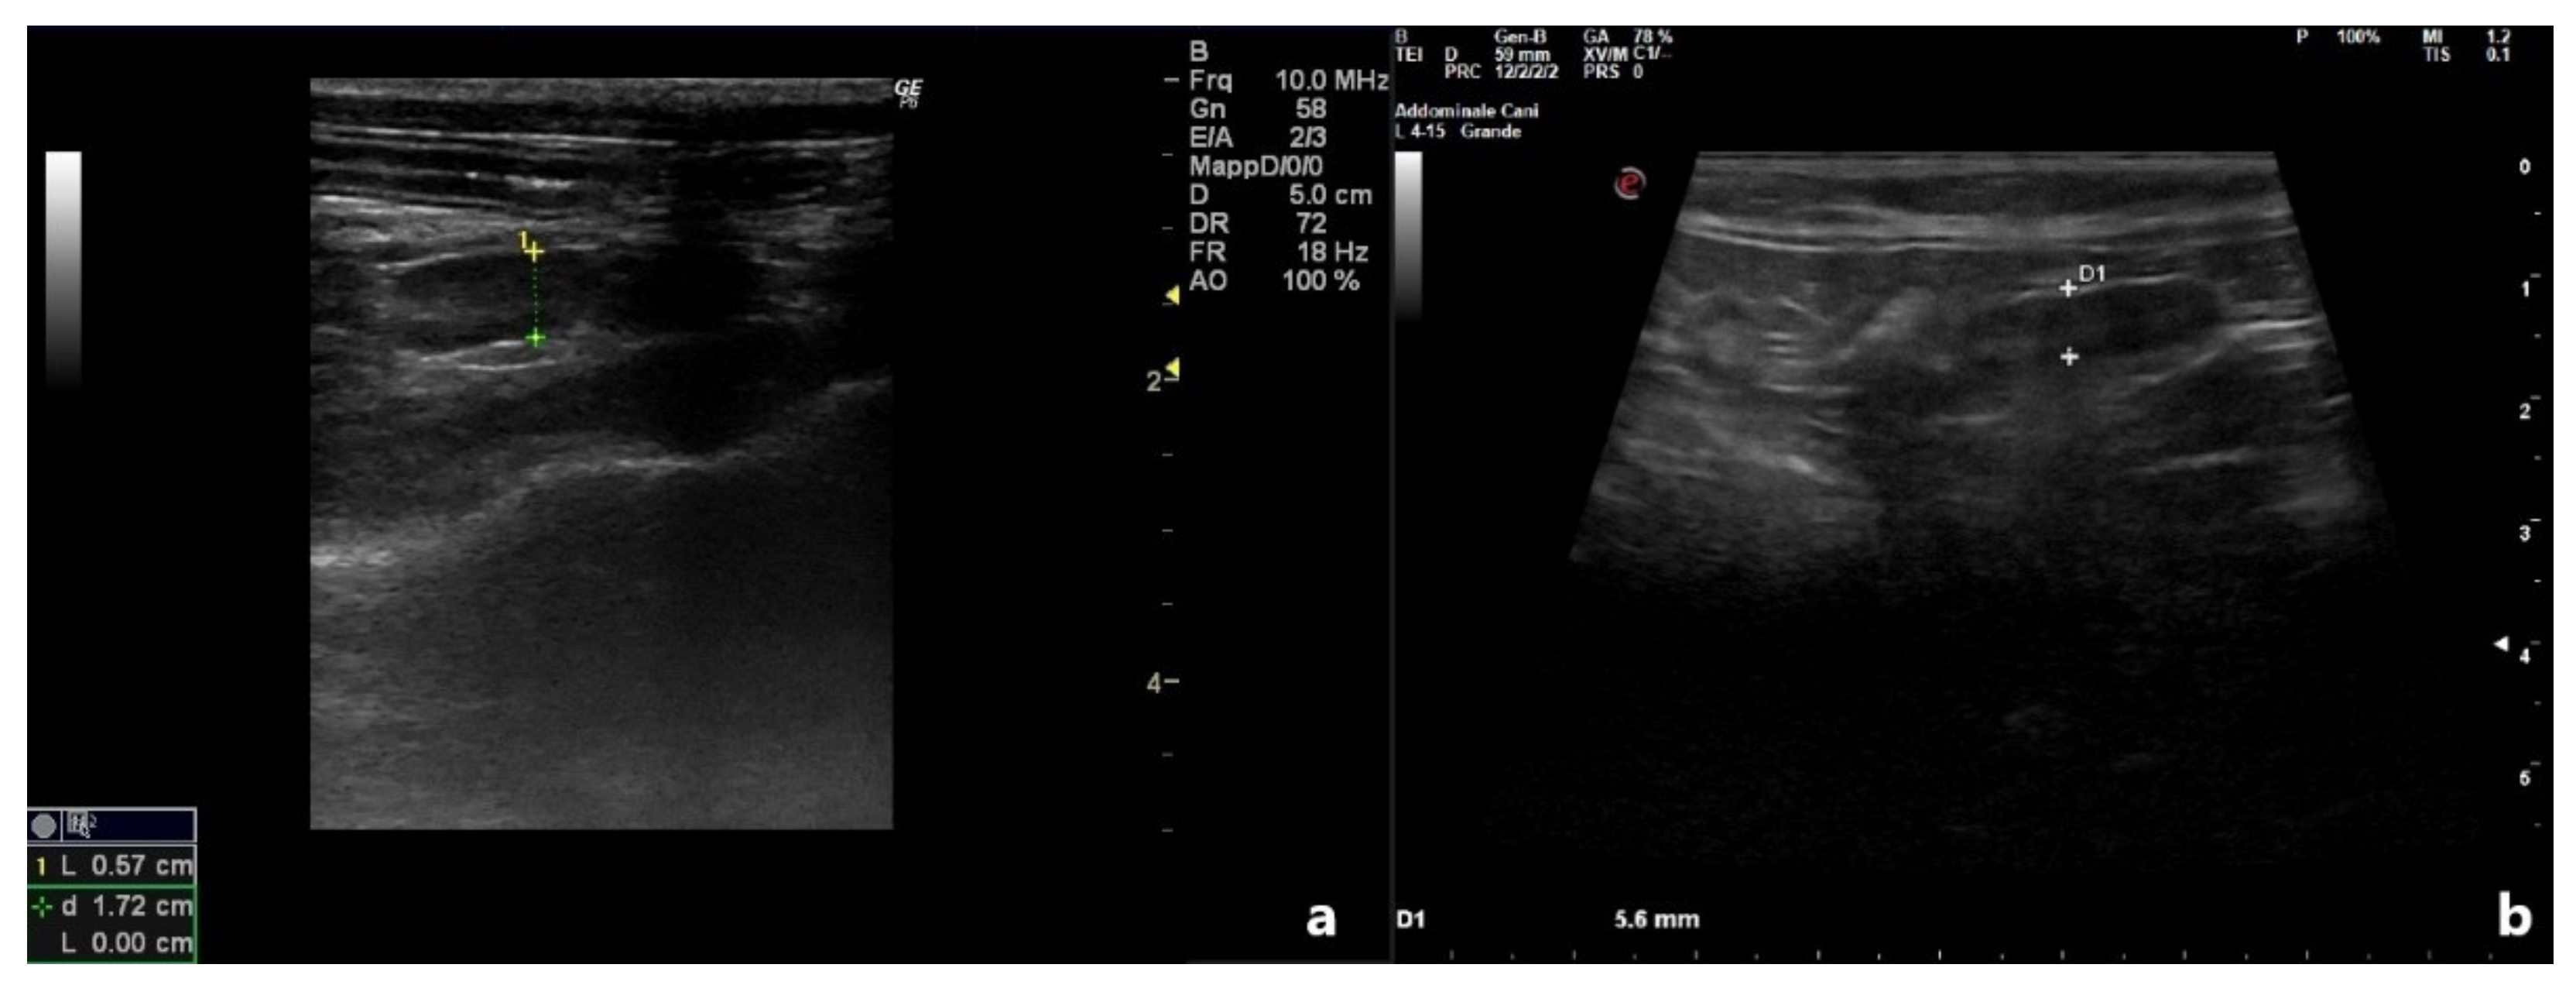

| Uterine Diameter (cm) | Uterine Wall (cm) | Luminal Collection | ||||

|---|---|---|---|---|---|---|

| D0 | D10 | D0 | D10 | D0 | D10 | |

| Patient 1 | 0.75 | 0.49 | 0.2 | 0.05 | Hypoecoic | No |

| Patient 2 | 2.35 | 0.57 | 0.3 | 0.10 | Heterogeneous | No |

| Patient 3 | 0.41 | 0.23 | 0.1 | 0.1 | Anechoic | No |

| Patient 4 | 1.02 | 0.56 | 0.18 | 0.10 | Anechoic | No |

| Patient 5 | 0.80 | 0.37 | 0.15 | 0.10 | Hypoecoic | No |